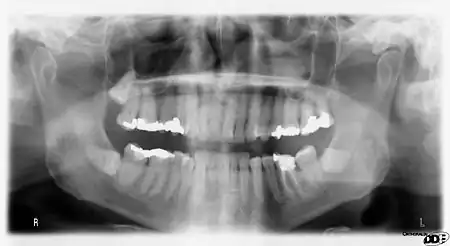

It is possible for both tooth decay and periodontal disease to be missed during a clinical exam, and radiographic evaluation of the dental and periodontal tissues is a critical segment of the comprehensive oral examination. The photographic montage at right depicts a situation in which extensive decay had been overlooked by a number of dentists prior to radiographic evaluation.